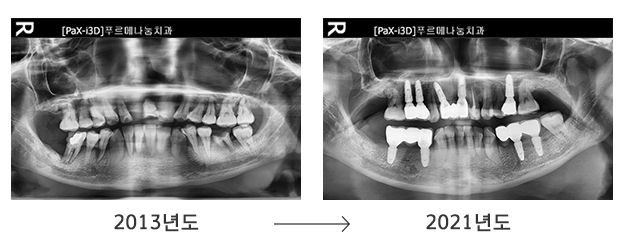

처음 푸르메치과의원을 방문했던 2013년, 2015년과 지금의 치아상태를 비교해보면 치아 보존 상태가 크게 악화된 것을 알 수 있습니다. 장애로 인해 신체의 불균형으로 치아가 비틀렸고 이갈이 습관으로 치아가 마모되고 망가진 것입니다. 비용 부담으로 미뤄왔던 치료는 결국 발치로 이어졌고 현재 남아있는 치아를 유지하기도 버거운 상황입니다.